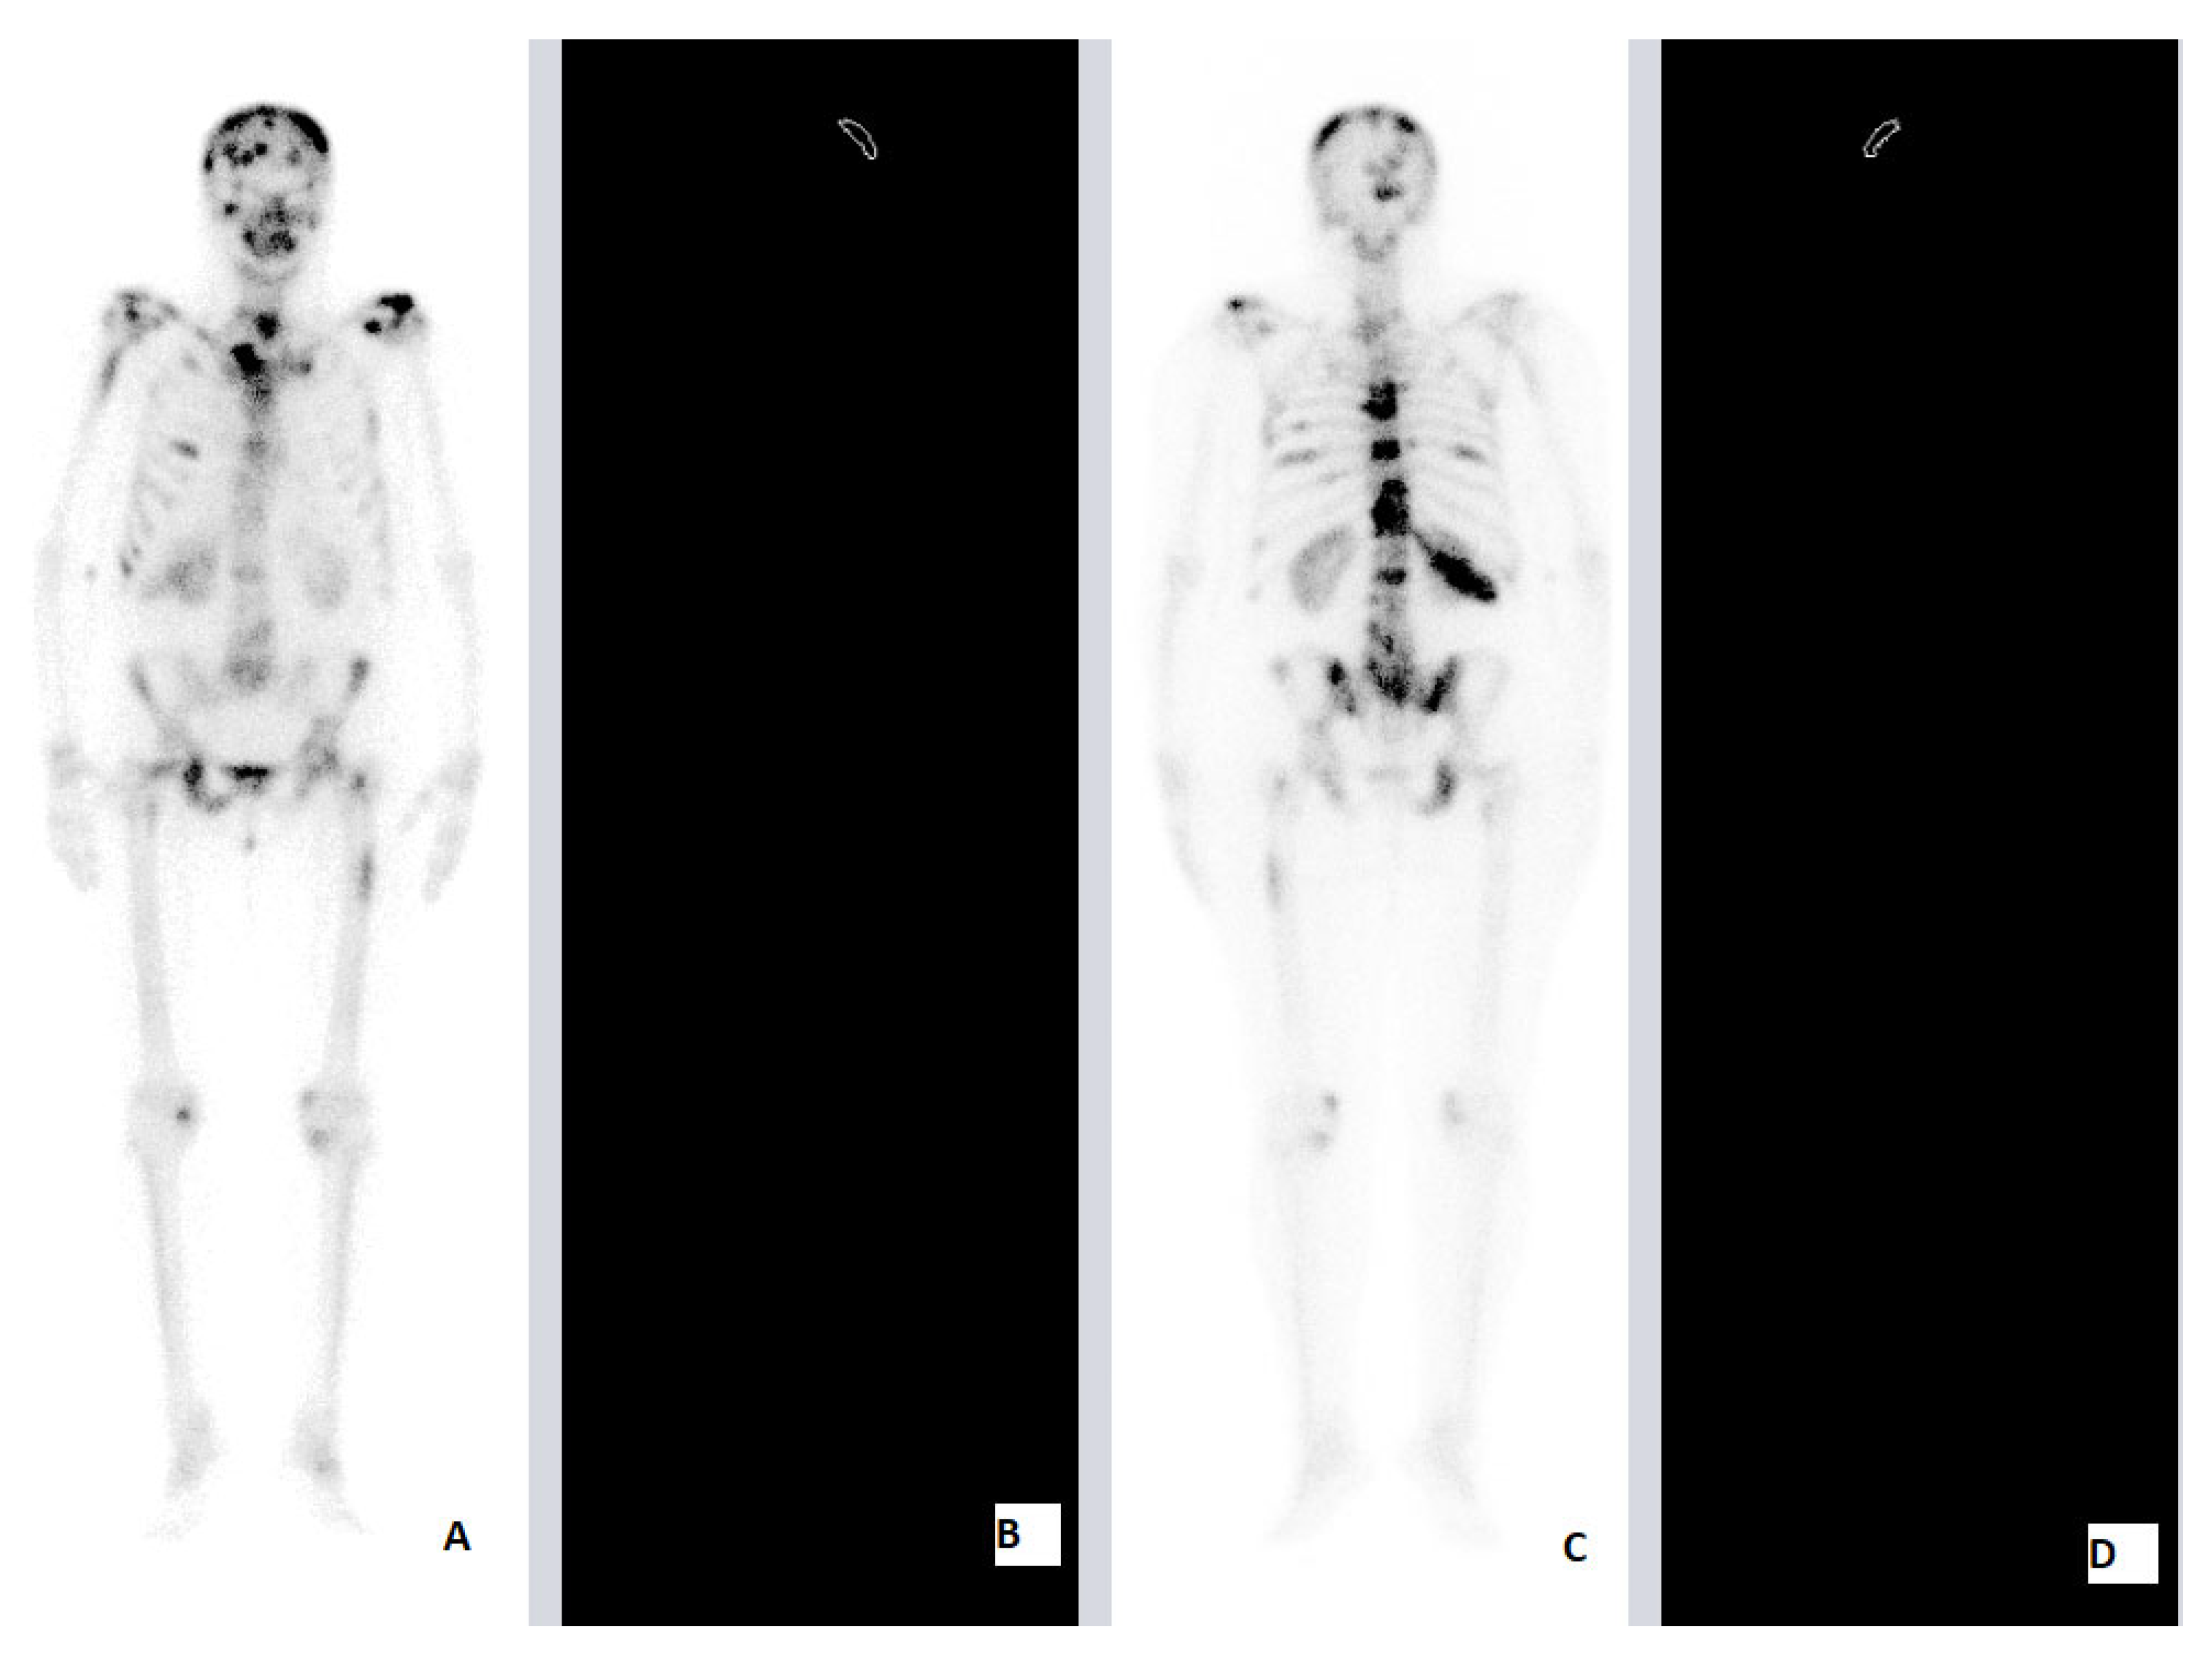

| SNCE | 69 | F | HFRT | 25 Gy (2.5 Gy) | Brain 12th TV 1st, 3rd, 5th LV 3rd, 7th Rhs Rib Rhs Tb Lhs Hmr LNMs | Brain | Lhs Hmr 7th Rhs Rib | 4 | 6 | ||